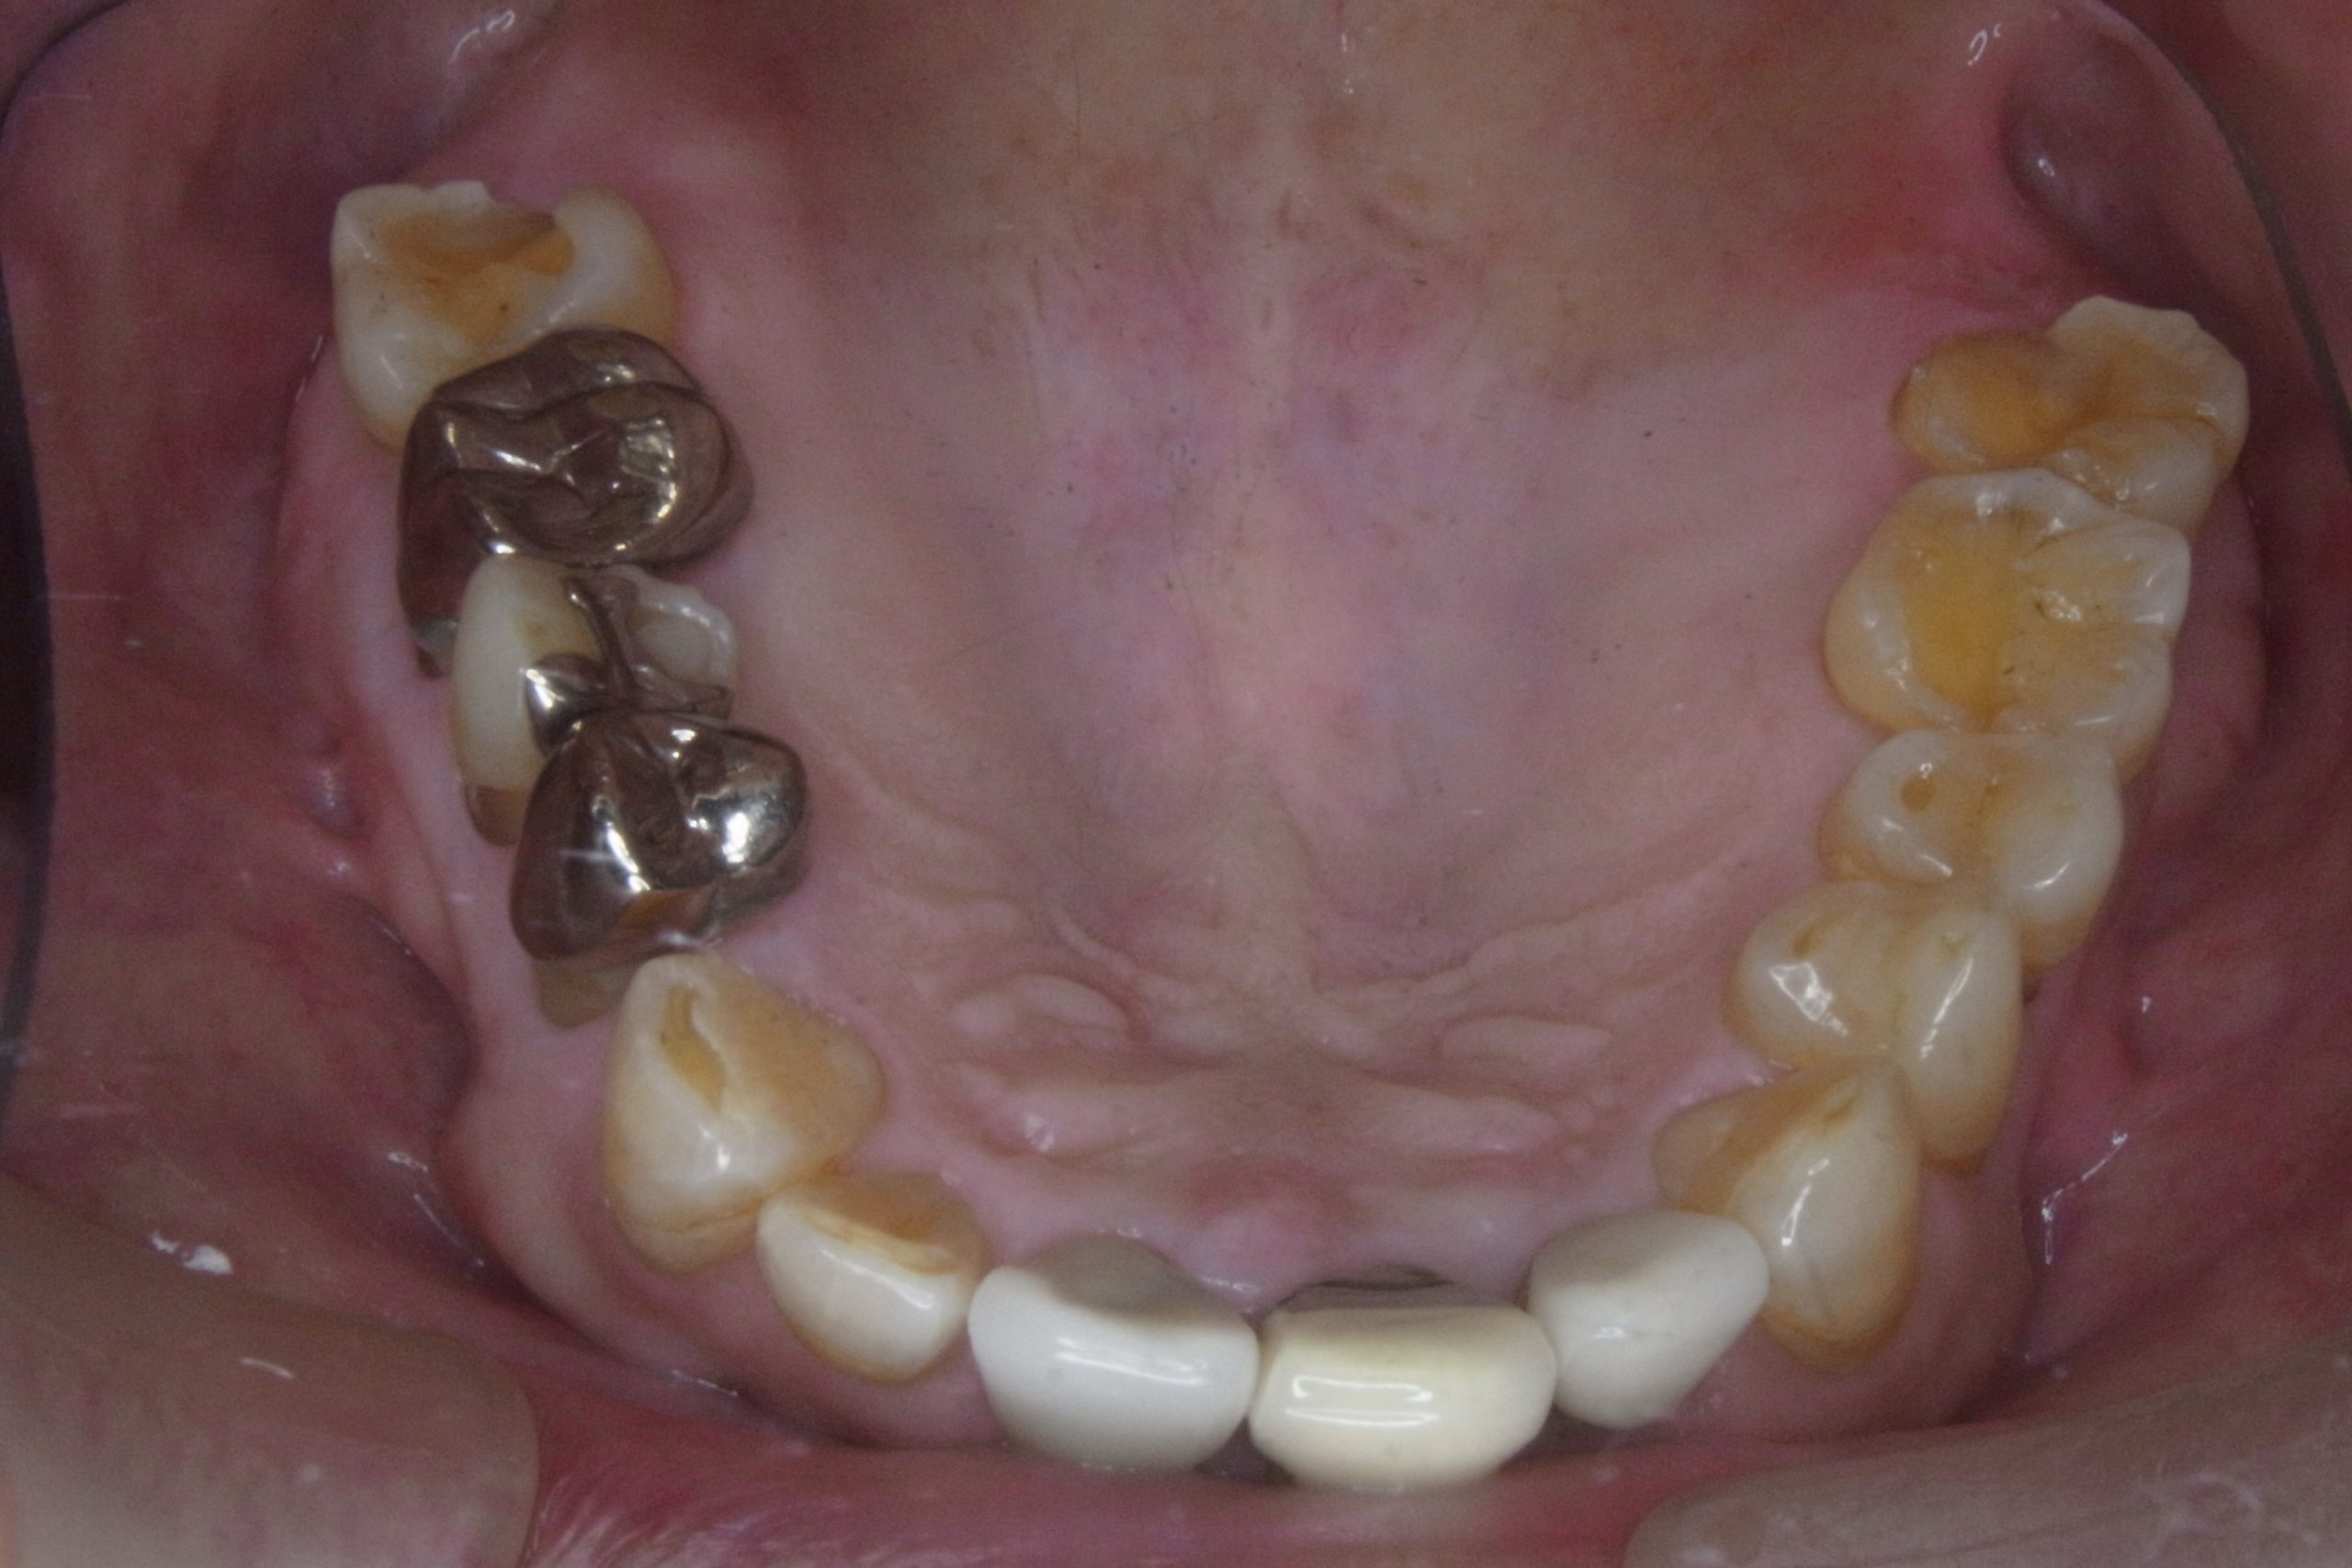

Before

歯がすり減ってしまい嚙み合わせが下がっています。

After

嚙み合わせを挙げる為に、ブリッジ等で被せ物をしました。何でも美味しく食べられるようになったとおっしゃっています。